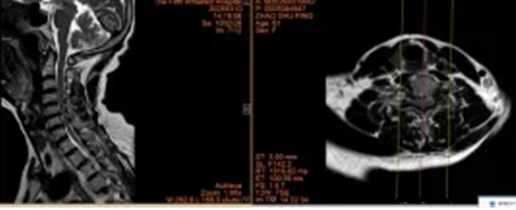

2.山西省晋城市沁水县龙港镇 44岁李女士

术前:依托高分辨率CT、MRI及神经电生理监测,进行三维可视化手术规划

术中:在超声骨刀辅助下开展颈前路、颈后路或后路+前路等术式,并在神经电生理监护下确保减压彻底、置钉安全。